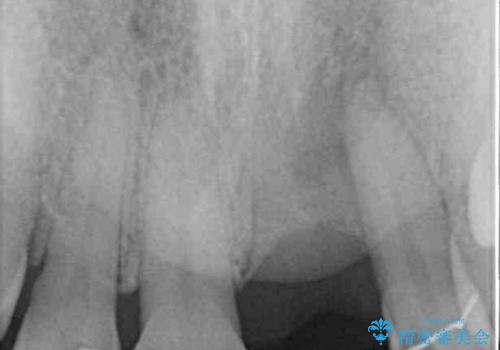

矯正治療により前歯横幅のバランスを整えた後に、上顎前歯をオールセラミックブリッジにて補綴治療を行うこととしました。

舌突出癖により、上下前歯が突出して離開してしまったため、舌のトレーニングを徹底的に行いました。